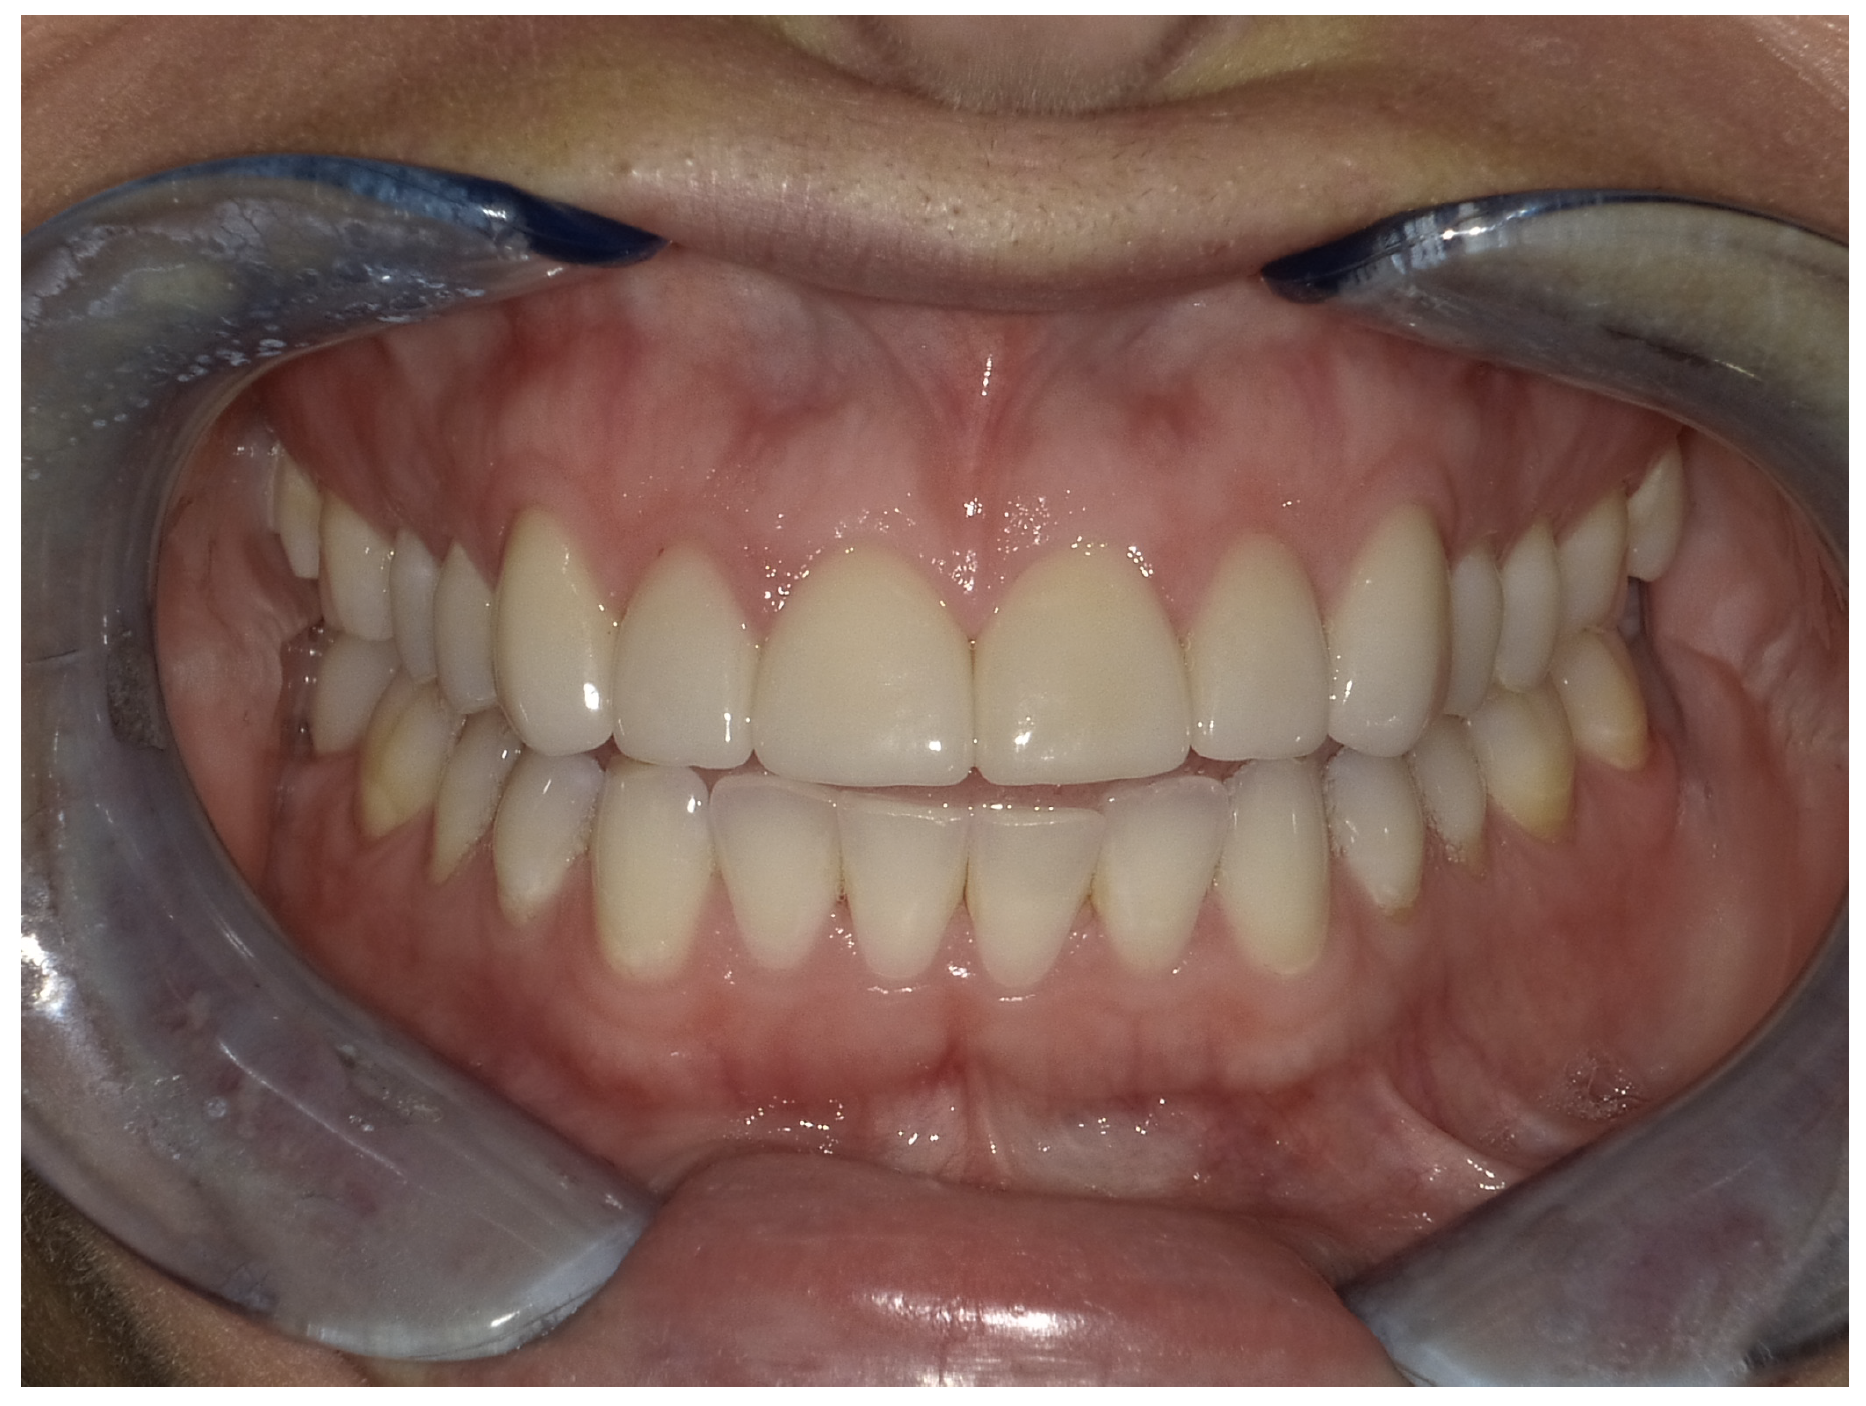

For the case in Figure 9 through Figure 11, the patent presented for an initial consultation with bonding completed on teeth Nos. 7 through 10 a few years prior with a chief complaint of not liking the way the resin bonding looked and how it was wearing. Up to this point, the bonding had repeatedly chipped and been repaired three times already. The patient's canines also exhibited signs of incised wear and flattening, which she did not like. Based on the patient's goals for her smile and her financial budget, she elected to have porcelain veneers completed on teeth Nos. 6 through 11. The total esthetics of the case design were somewhat limited given that the patient's esthetic zone included her posterior teeth and mandibular anterior teeth. Therefore, the color and characteristics of the veneers had to match her existing dentition closely.

In another case, the patient presented with very thick, bulky, over-contoured veneers done on teeth Nos. 7 through 10 when she was a teenager. There also was some recession and staining at the margins (Figure 12). The clinician decided to restore teeth Nos. 6 through 11. A preparation design was required with provisionals removed. As tooth structure could not be regrown, the practitioner made the best of the situation. There was good gum health, which is important for isolation and marginal seal. The clinician cemented with a universal, doing six units at one time. Minimal cleanup was required. At a 1-month follow-up visit, although tissue still was settling in, the contours were natural. After a year (Figure 13), the gum filled in nicely and was in excellent health, and there was good color stability and seamless marginal integrity.